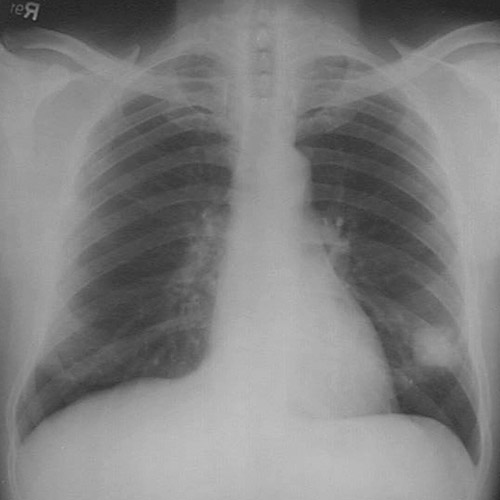

This chest radiograph demonstrates a mass lesion in the right lower lobe. This proved to be a "non-small cell carcinoma" which was best termed large cell anaplastic carcinoma.